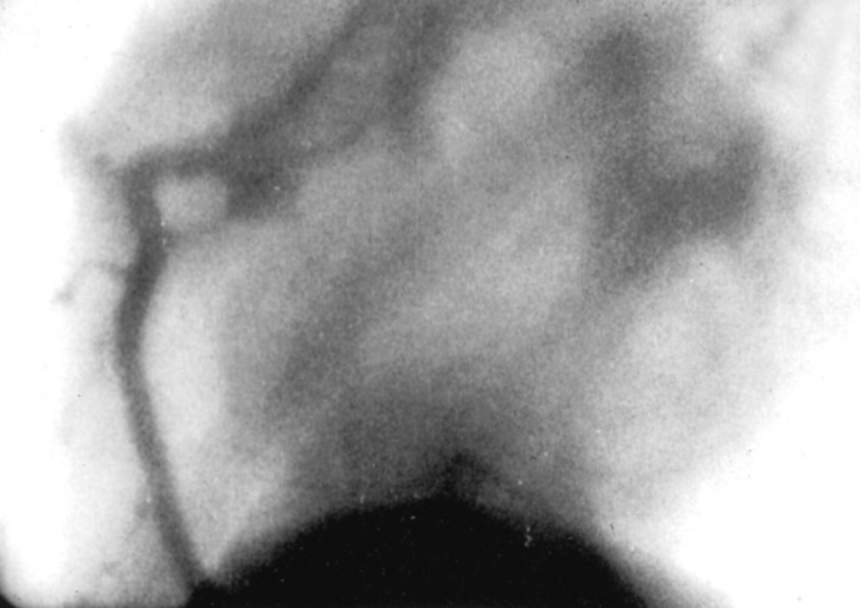

Mason Sones fu colui che eseguì la prima arteriografia coronarica il 30 ottobre del 1958.

Possiamo dire in un modo del tutto casuale.

Quando accidentalmente il mezzo di contrasto finì all’interno della coronarica di destra. Image

Malgrado l'errore il cuore non andò in fibrillazione.

Da quell’esperienza Sones comprese che piccole quantità di mezzo di contrasto non erano mortali per i pazienti.

Ciò avrebbe permesso di studiare meglio l’albero vascolare cardiaco.